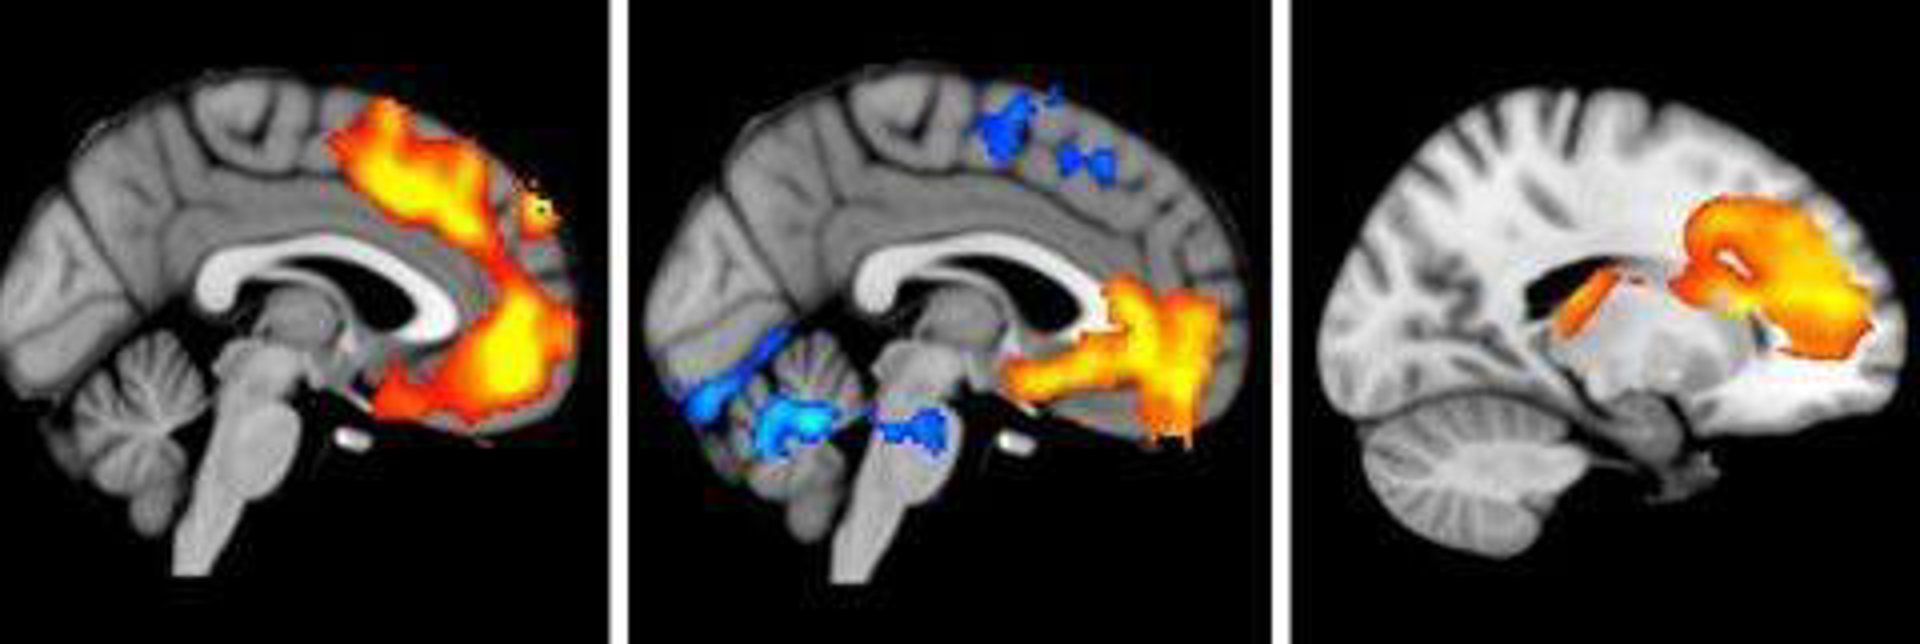

Anomalias cerebro

Los investigadores han descubierto que la cuprizona destruye la mielina a través de un mecanismo desconocido hasta el momento. Según los autores, este componente induce a los neutrófilos, una población específica de glóbulos blancos, a entrar en el sistema nervioso central y eliminar a los oligodendrocitos (OL), las células que forman la mielina. Es por ello que estas células sanguíneas podrían dirigirse al desarrollo de nuevos fármacos para la esclerosis múltiple.

La esclerosis múltiple es principalmente un ataque autoinmune sobre la mielina, el aislamiento clave de los tractos nerviosos. El daño más grave en la enfermedad sin embargo se cree que está causado por una combinación de mecanismos autoinmunes y tóxicos. En ratones, la cuprizona química produce este tipo de daño grave a la mielina.